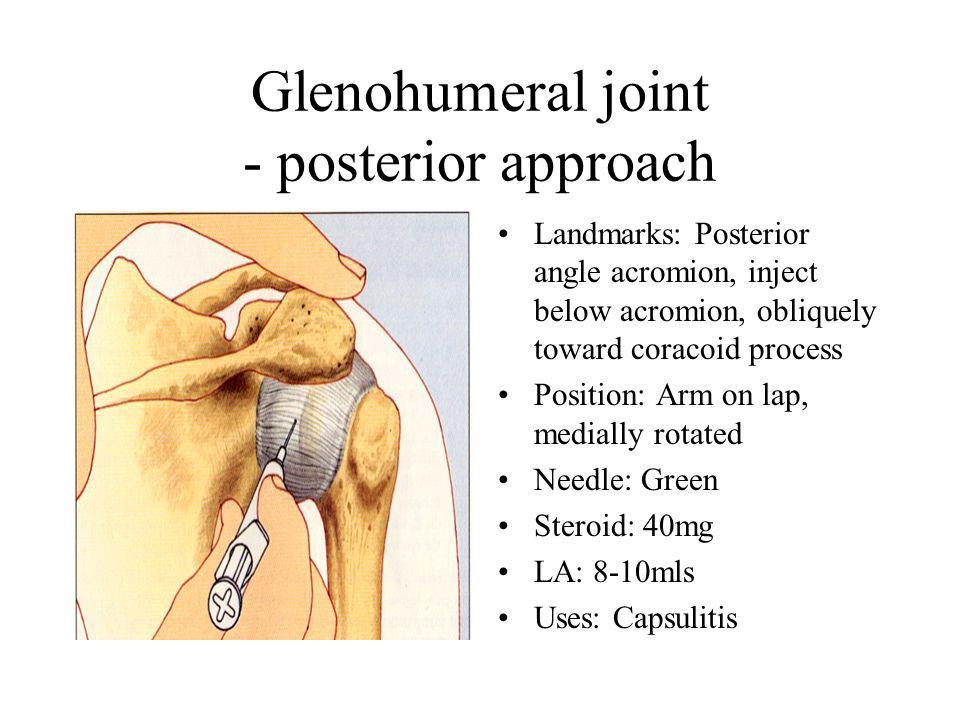

Glenohumeral ligament: анатомия и функции плечевого сустава